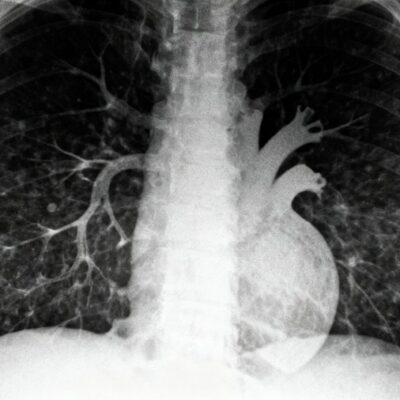

Before starting a new job or returning after a health-related absence, employers often require proof that you are physically capable of performing your ...